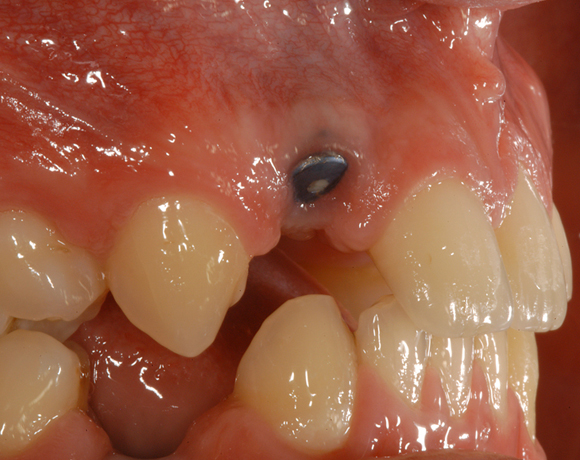

Der vorliegende Patientenfall war noch mit einem Prototypen eines vollkeramischen Aufbaus versorgt worden. Deutlich sichtbar der dunkle Rand an der VMK – Krone der metallkeramischen Versorgung. Die dunkle Verfärbung der Gingiva ist durch ein Amalgamtätoo bedingt.